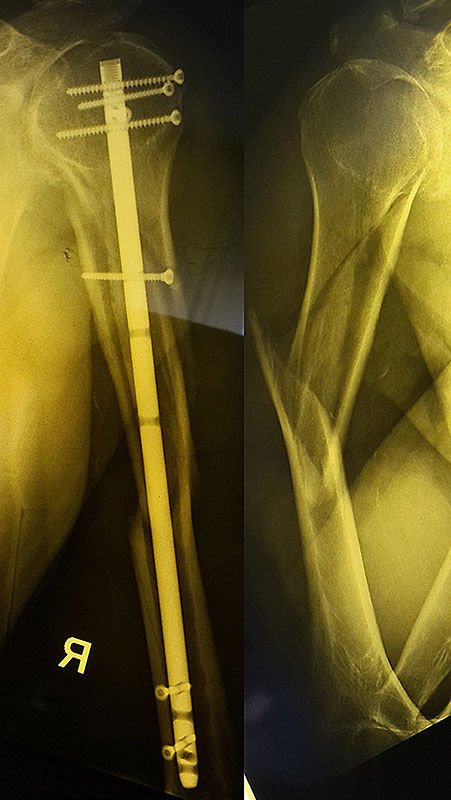

Для лечения перломов используется различные разновидности фиксаторов. Блокируемые стержни используются при переломах дифиза и позволят достигнуть требуемого эффекта при минимальных разрезах кожи.

Пациент Р. 68 лет. Травма в результате падения на улице. На 2 сутки выполнен остеосинтез плечевой кости.

Пациент Г. 72 года. Травма в результате ДТП (пешеход). В 1 сутки выполнен малоинвазивный остеосинтез стержнем с блокированием. На 3 сутки пациент выписан из стационара в удовлетворительном состоянии. Швы сняты через 12 дней. Признаки консолидации перелома через 12 недель.